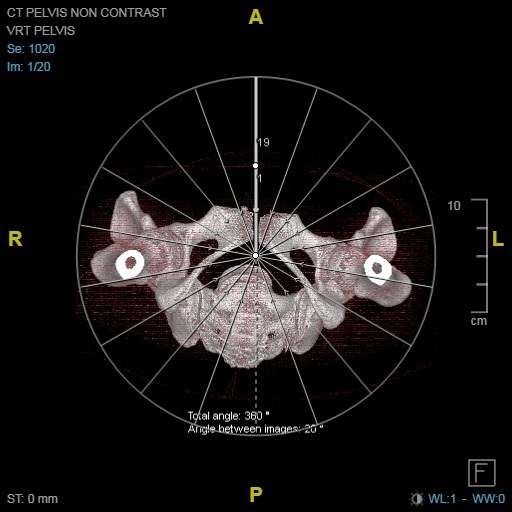

Series of Images Send to SyngoVia

- Pelvis 1.0 B31f

Series of Images Send From SyngoVia to PACS

- Radial ranges of pelvis

- VRT Range Tilt Pelvis

- VRT Pelvis